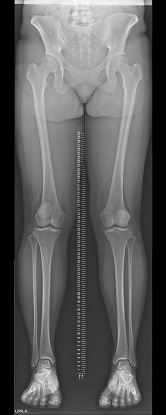

一般撮影

単純X線撮影は一般的に「レントゲン」といわれている検査です。主に胸部・腹部・骨格系の撮影を行います。全ての撮影室で最新のFPD(FPD:Flat Panel Detector)を使用しており、従来よりも被ばく線量が少なく、鮮明な画像を提供しています

• 下肢全長画像